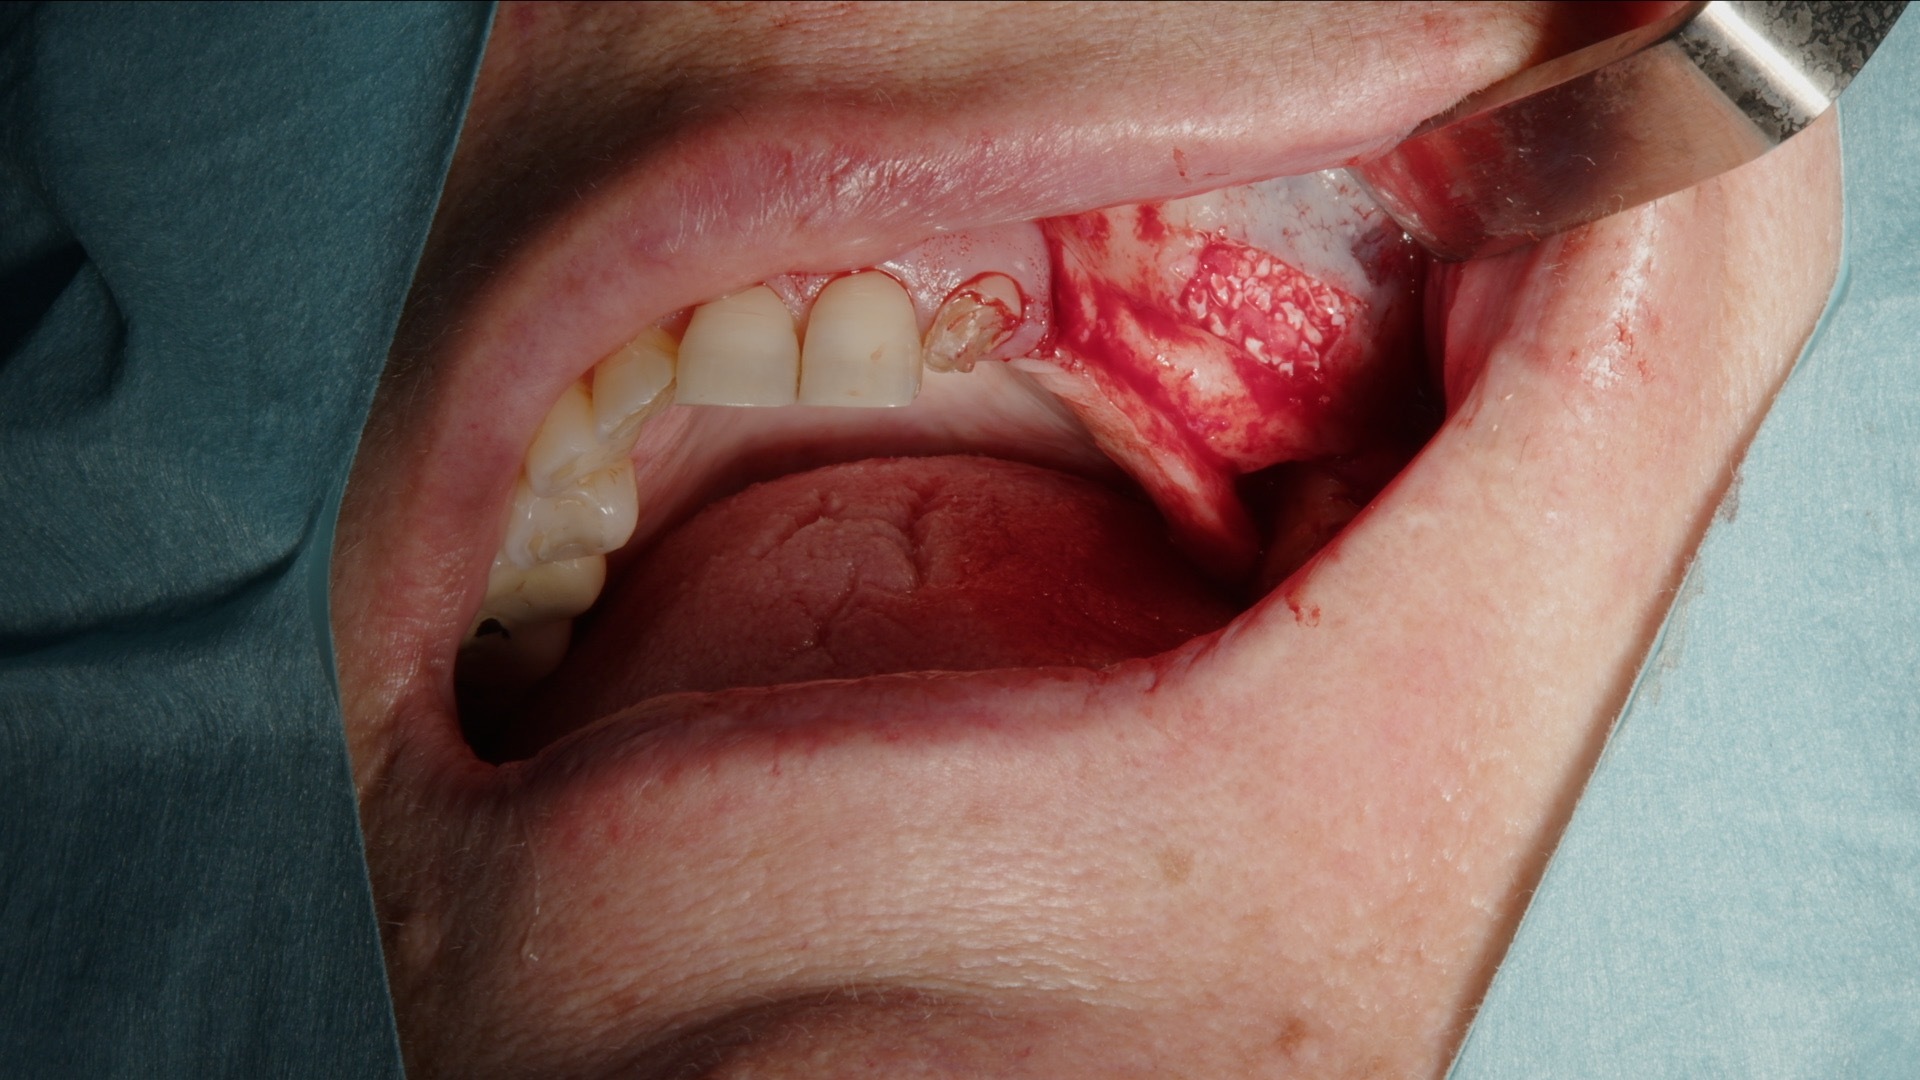

Det laterala fönstret prepareras konsekvent med Acteon Piezo Cube och diamantspets. Den piezoelektriska tekniken möjliggör selektiv benbearbetning med hög precision och minimal risk för skada på mjukvävnad och sinusmembran. Instrumentet är ergonomiskt, lätt att manövrera och ger god taktil kontroll, vilket bidrar till ett effektivt och tryggt arbetsmoment.

2. Preparering av lateralt fönster med Acteon Piezo Cube och diamantspets.

3. Skonsam elevation av sinusmembranet med piezo-lyftspets.

4. Fullt preparerat lateralt fönster inför augmentation.